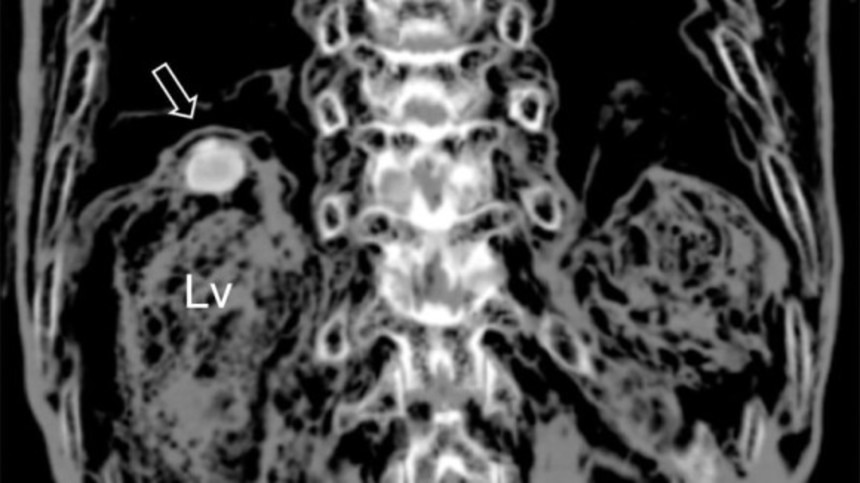

韓国の檀国大学校のミン・セオ(Min Seo)氏が率いる調査チームは、ジン・リーの子孫の許可を得たうえで、ミイラ化した遺体をCTで調査した。

すると肝臓に変わったしこりがあることがわかり、摘出したところ各85ミクロン長の褐色の卵が発見された。

卵はウェステルマン肺吸虫(Paragonimus westermani)のものだった。

このことはジン・リーが肝臓肺吸虫症を患っており、それがもとで死亡したことを示唆している。セオ氏によると、この症状を患ったこれまでに知られている患者としては最高齢の人物である。